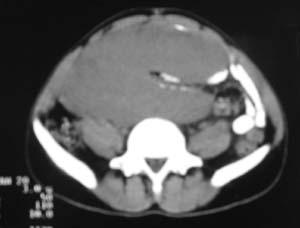

以下是引用老林在2007-9-27 22:11:00的发言:[br]肠系膜间质瘤可能大,建议增强

以下是引用余辉在2007-9-27 22:24:00的发言:[br]暂考虑肠道间质来源肿瘤如小肠平滑肌肉瘤/瘤可能,应该增强